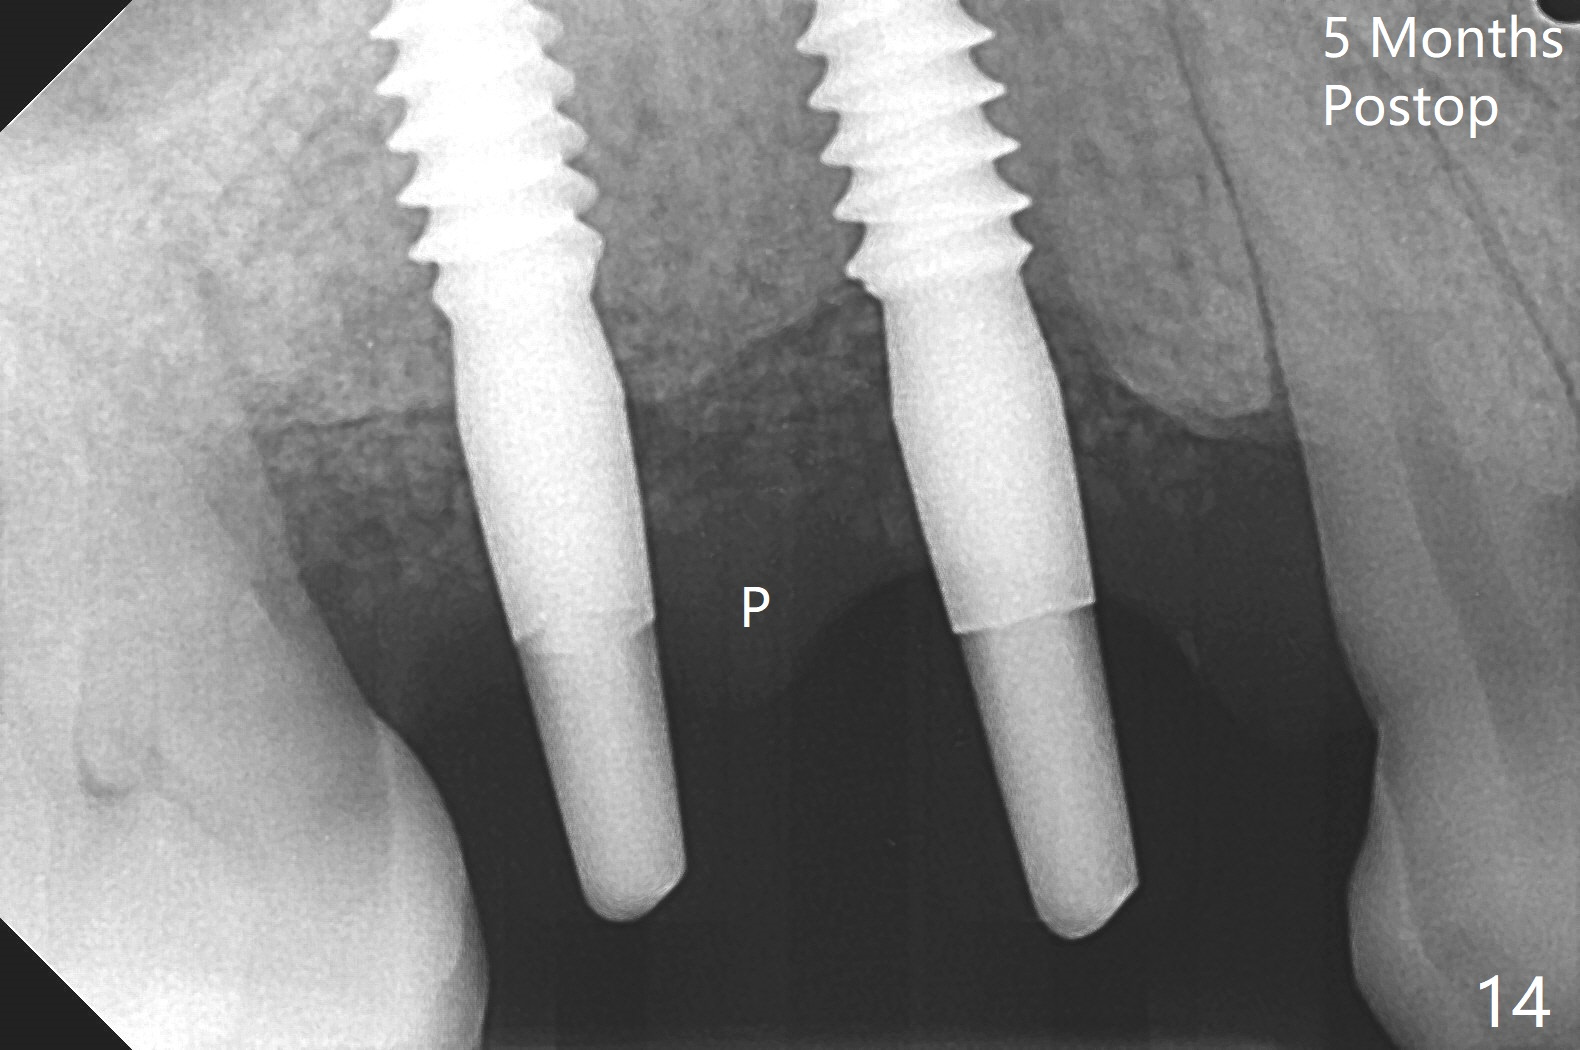

术前CT显示右上4牙槽骨比5窄(图一,二),3.5毫米植体比较合适,况且牙龈厚,基台长的一段式植体显得得当。为了取得最好的植体方位,4先拔除(图三),种植(图四),调整后者深度后,拔除5(术前征求病人同意),开始钻洞(图五),完成种植(图六)。粘性骨粉不仅放置于植体周围,而且6牙根近中(图七),4/5牙槽嵴和龈乳头(P)之间,减少术后龈乳头萎缩(图八:*)。制作两个分开临时牙冠,有利于维持龈乳头。对于病人来说,临时牙冠帮助咀嚼,而对侧拔牙创无法吃饭。术后3个月两个分开临时牙冠(其中一个龈方移位(图九:箭头)保持龈乳头(*)和牙龈外形(图十:*)。临时牙冠取出后,调整基台高度,少量钛屑(不妨大局)附着在健康的牙龈沟(图十一),再次显示两个基台之间龈乳头(图十二:*),衬里,修整的临时牙冠又插回牙龈沟(图十三:箭头),继续维持软组织形态,准备一个月后,调整基台边缘(图十二:箭头),取模。术后五个月大部分骨粉依然保留在植体和邻牙周围,龈乳头退缩不多(图十四: P)。三个月后(术后六个月)钛削无影无踪(图十五,与图十一对比))。永久性牙冠周围空间慢慢会消失(图十六,使用临时性胶水)。